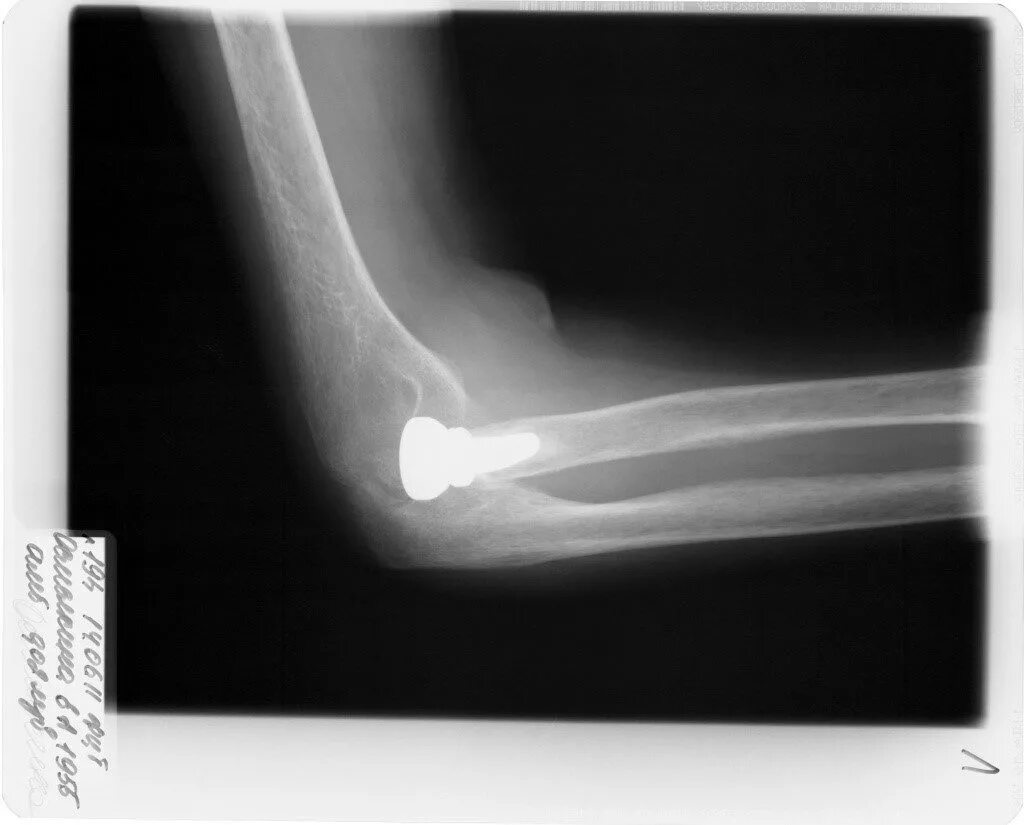

Перелом локтевой